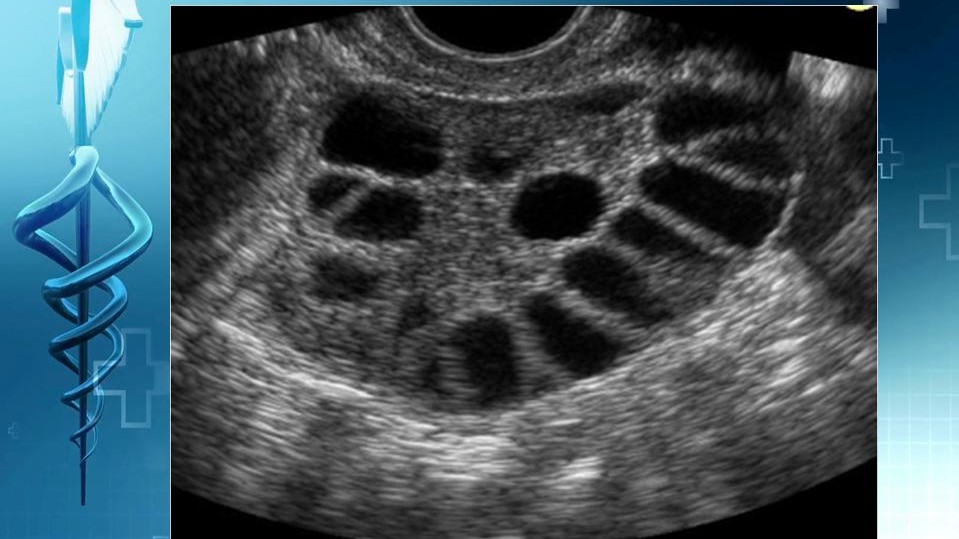

A kórkép névadó tünetének észlelése, az ultrahanggal felfedezhető polycystás petefészek szerkezet (PCO), nem azonos a szindrómával (PCOS). Nőgyógyászati ultrahang vizsgálat során az ovariumok polycystas szerkezete nem ritka, populációs vizsgálatok szerint prevalenciája elérheti a 21 %-ot. (G.S.)

A Rotterdam konszenzus (2003) és az Androgen Excess Sociaty PCOS Society (2006) ajánlása szerint a petefészek szerkezetének ultrahangos vizsgálata a PCOS diagnózisának egyik alapvető kritériuma. Ugyanakkor a petefészek szerkezetének ultrahangos vizsgálatának diagnosztikus értéke gyakran megkérdőjelezhető. A petefészek ugyanis normális lehet a PCOS-ban, és fordítva, a policisztás petefészek morfológiát (PCO) a szindróma nélküli nőkben is meg lehet figyelni. A pubertástól kezdve, különböző mértékben, de mindenkinek "cisztás" a petefészke. Ezek a ciszták - az esetek többségében - a fejlődés különböző fázisában lévő tüszők. Ezért serdülőkorban, főleg 17 évesnél fiatalabb lányoknál, nem is javasolt a rutin ultrahangos vizsgálat a petefészek polycystás szerkezetének megítélésére.

Általánosan elfogadott, hogy a PCOS-ban szenvedő nők általában nagyobb petefészekkel rendelkeznek, megnövekedett tüszőszámmal. A konkrét diagnosztikai határérték azonban az utóbbi években is vita tárgya volt. A most ismertetett diagnosztikai kritériumok a 2018-ban megjelent, bizonyítékokon alapoló irányelvben szerepelnek (International evidence-based guideline for the assessment and management of polycystic ovary syndrome 2018), olyan ultrahangvizsgálatok eredményei alapján, ahol a vizsgálatok magas frekvenciájú endovaginális fejjel történtek.

1. a tüszők száma petefészeknél (FNPO) ≥ 20,

2. a petefészek térfogata ≥10 ml, nincsennek ciszták, sárgatest vagy domináns tüszők.

Vannak olyan kutatások is, amelyek a normál és a PCOS betegek egyértelmű elkülönítésére a 12 follikulus helyett legalább 26 follikulust szükséges igazolni petefészenként (26>FNPO). Az új FNPO kritérium szenzitivitása: 85%, specificitása: 98%. Az új diagnosztikus kritérium azonban csak az új típusú ultrahangkészülékek (transducer frekvenciája ≥8 MHz) esetén alkalmazható.

A megadott linken normális és PCO szerkezetű petefészkek képei látható (4. kép), HA A KURZORT MOZGATJÁK. A két képet összehasonlítva egyértelműen felismerhető a normál és a PCO szerkezetű petefészkek közötti különbség.